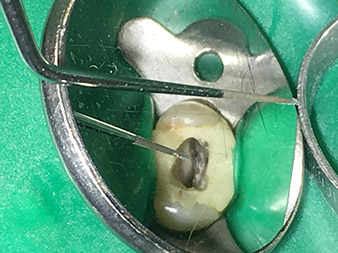

Dr. Nouraie: The use of ultrasonic tips allows targeted, atraumatic, minimal removal of substance at the desired site (e.g., when exposing the canal openings, rounding off the cavity floor and exposing broken-off instruments or posts as well as when processing coronal canal sections).

Canal transitions can be smoothed and rounded off with more precision than when using burs. The activation of the rinsing fluid in particular offers enormous advantages that cannot be guaranteed with other instruments. The special instruments from W&H make it possible to perform completely new indications minimally invasively such as revision of broken-off tips and posts.

Visual aids such as dental loupes or even better a surgical microscope should be employed for all indications in the canal. In addition, I also think it is important that all the applications in the canal – with the exception of the activation of the rinsing fluid – are performed by specialized colleagues with corresponding experience and the necessary expertise in the field.